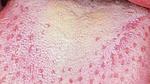

- ظهور علامات بيضاء ذات ملمس خشن على سطح اللسان، أو الحلق، أو اللوز، أو داخل الخد.